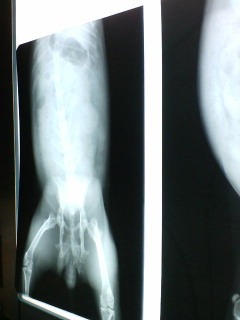

42848410.jpg“おかるの中身”

でも特に異常は見つからず

目薬もらって帰宅♪

ウサギさんは、犬ほどまだ医学が発達してないから、むやみに治療すればいいってわけじゃないんだってー